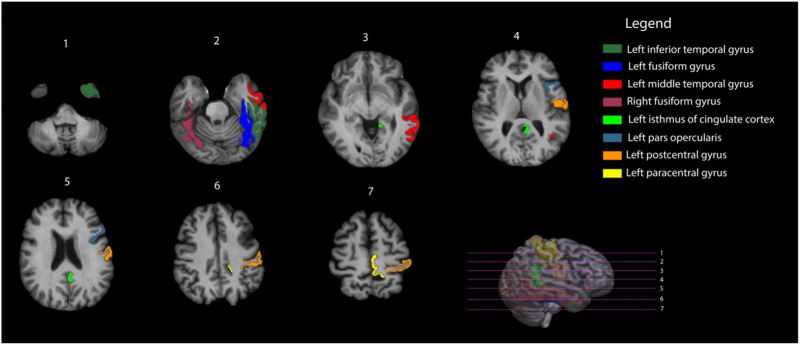

大脑通过相互连接的区域网络运作,神经胶质肿瘤及其治疗可能会破坏这些区域。这项研究调查了神经胶质瘤中这种改变的功能网络拓扑与认知之间的关系。我们研究了50名成年胶质瘤幸存者(治疗后1年)和50名健康对照。参与者接受了六个领域的认知评估和8分钟静息状态功能MRI。基于BOLD信号,计算了78个脑区之间的部分相关性。根据它们的绝对值,导出全脑和节点图度量并归一化为随机图。采用Mann-Whitney U检验和混合设计方差分析分别评估全脑和节点图指标的组间差异。组间差异显著的指标与认知评分相关,p < 0.050为显著性差异。在对照组中,78个节点中有8个被确定为枢纽。患者表现出更高的全脑聚类,与智力(r(98) = -0.409, p bonf < 0.001)和执行功能(r(98) = 0.300, p bonf = 0.014)相关。在患者中也观察到较低的中心性,较高的节点聚类和分类性,特别是在中心,分别与语言和执行功能相关(所有r(98) bb0 0.300, p < 0.050)。神经胶质瘤患者通常会经历认知缺陷以及治疗后功能网络拓扑结构的改变。聚类性、分类性和中心性的改变可能作为补偿机制,显著影响认知功能。

The brain operates through networks of interconnected regions, which can be disrupted by glial tumors and their treatment. This study investigates associations between this altered functional network topology and cognition in gliomas. We studied 50 adult glioma survivors (>1-year posttherapy) and 50 healthy controls. Participants underwent cognitive assessments across six domains and an 8-min resting-state functional MRI. Based on the BOLD signal, partial correlations were computed among 78 brain regions. From their absolute values, whole-brain and nodal graph metrics were derived and normalized to random graphs. Group differences in whole-brain and nodal graph metrics were assessed with Mann-Whitney U tests and mixed-design analyses of variance, respectively. Metrics exhibiting significant intergroup differences were correlated with cognitive scores, with p bonf < 0.050 indicating significance. Among controls, 8 of 78 nodes were identified as hubs. Patients exhibited significantly higher whole-brain clustering, correlating with intelligence (r(98) = -0.409, p bonf < 0.001) and executive functioning (r(98) = 0.300, p bonf = 0.014). Lower centrality, higher nodal clustering, and assortativity were also observed in patients, particularly in hubs, correlating with language and executive functioning, respectively (all r(98) > 0.300, p bonf < 0.050). Glioma patients commonly experience cognitive deficits alongside posttreatment alterations in functional network topology. Alterations in clustering, assortativity, and centrality may specifically act as compensatory mechanisms, significantly influencing cognitive functioning.